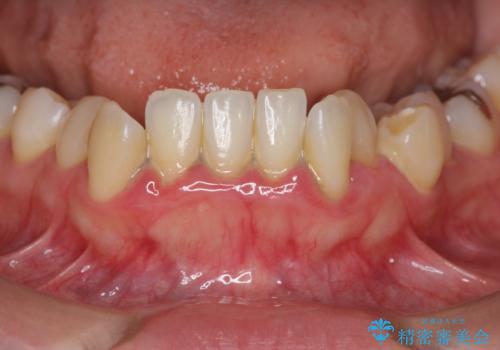

初診時、下顎前歯にびっしりとついていた歯石を除去することで歯肉の発赤・腫脹は治まり健康な状態になることができました。